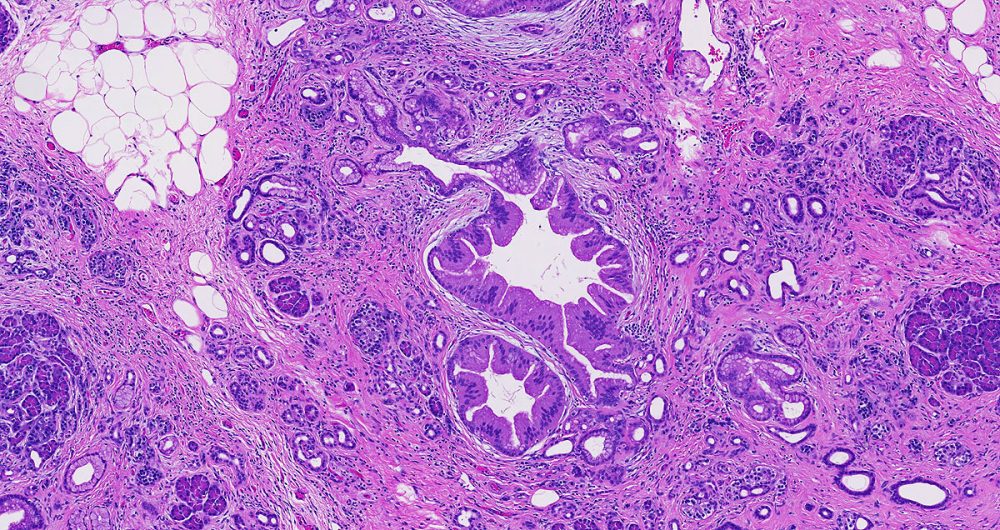

Low-grade pancreatic intraepithelial neoplasia encompasses three older terms- PanIN-1A, PanIN-1B and PanIN-2.